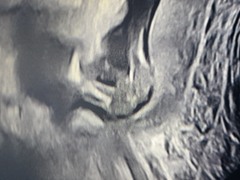

Well, like the sonographer said when I had my scan with my son, "I'm not allowed to confirm anything but I definitely see something consistent with a boy".

The big thick structure at the top is a femur. Coming down toward the right you have a tiny scrotum and can see a bit of penis poking off to the left.